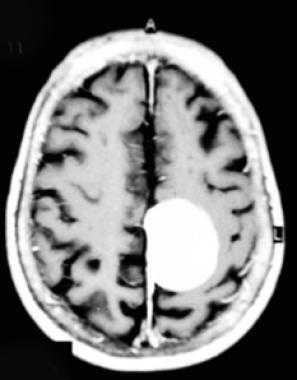

Фалькс-менингиома на МРТ.

А: на Т1-взвешенном МР-изображении отмечается солидное образование, характеризующееся изоинтенсивностью по отношению к твердой мозговой оболочке, инвазией в кость и сдавлением теменных зон коры.

В: На Т1-взвешенном МР-изображении с контрастным усилением видна частично контрастируемая опухоль.

С: На корональном Т2-взвешенном изображении видно изоинтенсивное образование, что соответствует плотной ткани. Такая картина характерна для фибробластных менингиом.

D : На Т1-взвешенном МР-изображении с контрастным усилением визуализируется гиперинтенсивное образование внутри мозгового вещества кости.